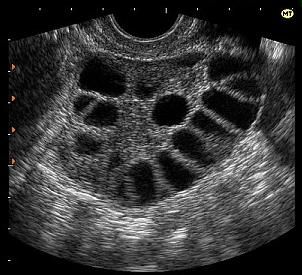

почему болит спина после месячных как при месячныхГиперстимуляция яичников

Синдром гиперстимуляции яичников (СГЯ) — редкое ятрогенное осложнение после стимуляции яичников (искусственная овуляция) с помощью вспомогательных технологий репродукции и других методов лечения бесплодия.

Симптомы СГЯ часто начинаются через 10 дней после инъекций и могут варьироваться от легкой до тяжелой формы, могут со временем ухудшаться или улучшаться.

Диагноз ставится на основании:

• Физического осмотра;

• Ультразвука. УЗИ покажет увеличение яичников;

• Анализа крови.

Он может развиваться у женщин, которые лечат бесплодие с помощью гормональных препаратов. Это состояние можно определить по увеличенным яичникам, образованиям фолликулярных кист, отекам стромы и другим признакам. При тяжелой форме отмечаются боли в пояснице после месячных, неприятные проявления в половых органах, вздутие живота, а также значительный набор веса. При сложной форме также появляется асцит, одышка, плевральный выпот и многое другое.